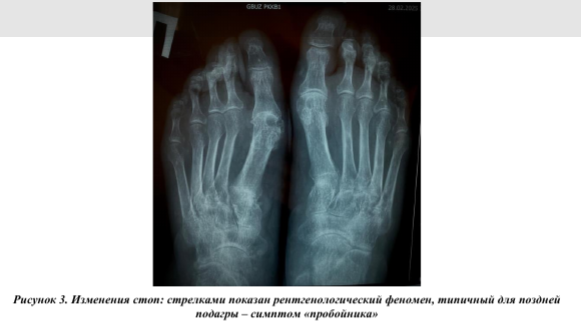

По данным рентгенографии коленных суставов выявлен двусторонний гонартроз II стадии, кистей - рентгенологические признаки артрита II стадии (Рис.2). На рентгенограмме стоп определялся выраженный остеопороз, суставные щели обоих плюсне-фаланговых сочленений равномерно сужены, уплотнены суставные поверхности, в проекции головок плюсневых костей - пробойники, что характерно для подагрического артрита слева II стадии, справа III-IV стадии (Рис.3).

По данным авторов, умеренные рентгенологические изменения суставов возникают в среднем через 9 лет, а более значительные через 10-15 лет и более [5]. У наблюдаемой нами пациентки рентгенологические изменения были выявлены уже через 5 лет от начала заболевания.